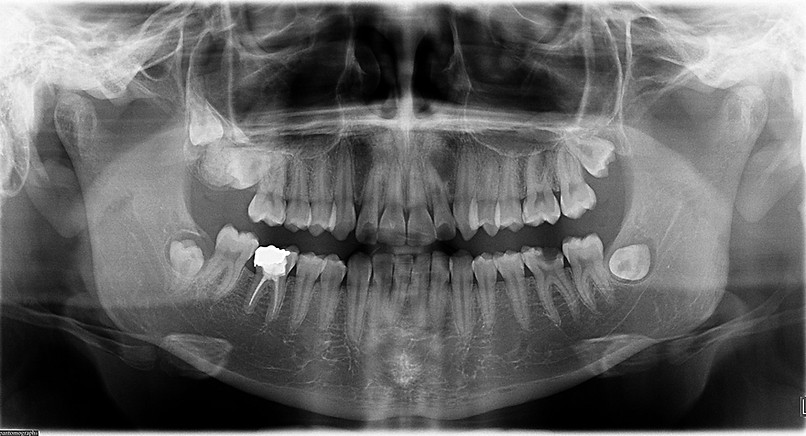

ODONTOMA 2.1.jpg

ODONTOMA 2.jpg